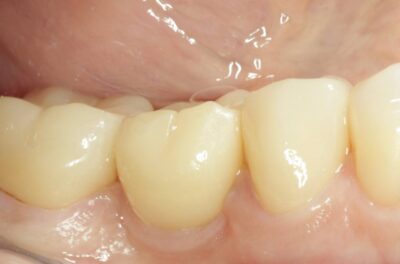

Протезирование коронками из диоксида циркония, после эндодонтического лечения — Исламов Л.А.(01.04.2026)